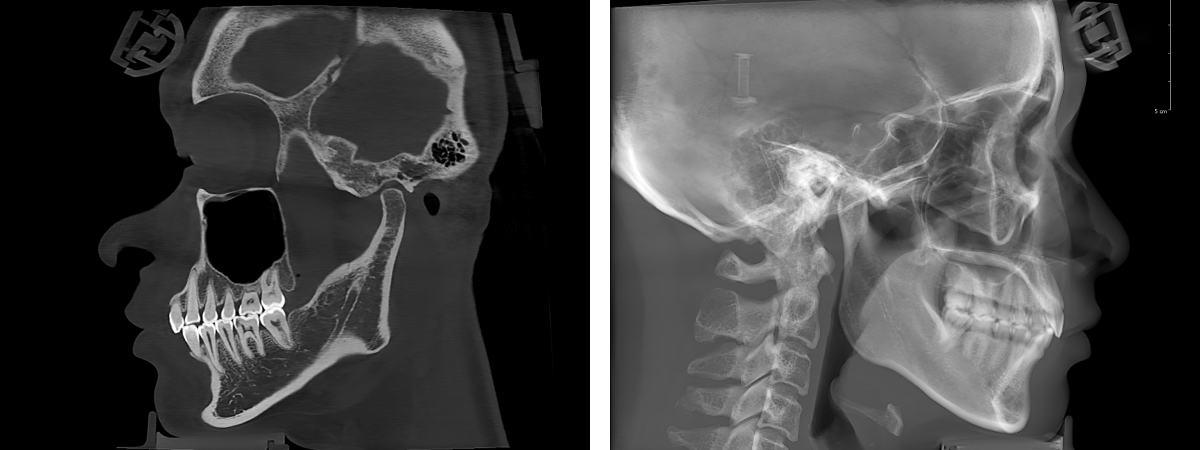

The 20 × 18cm FOV, can fully cover the range from the top of the forehead, down to the neck angle (up to the 4th cervical vertebra), and from the front to the tip of the nose. Even for patients with overweight and larger facial shapes, this FOV is effortless.